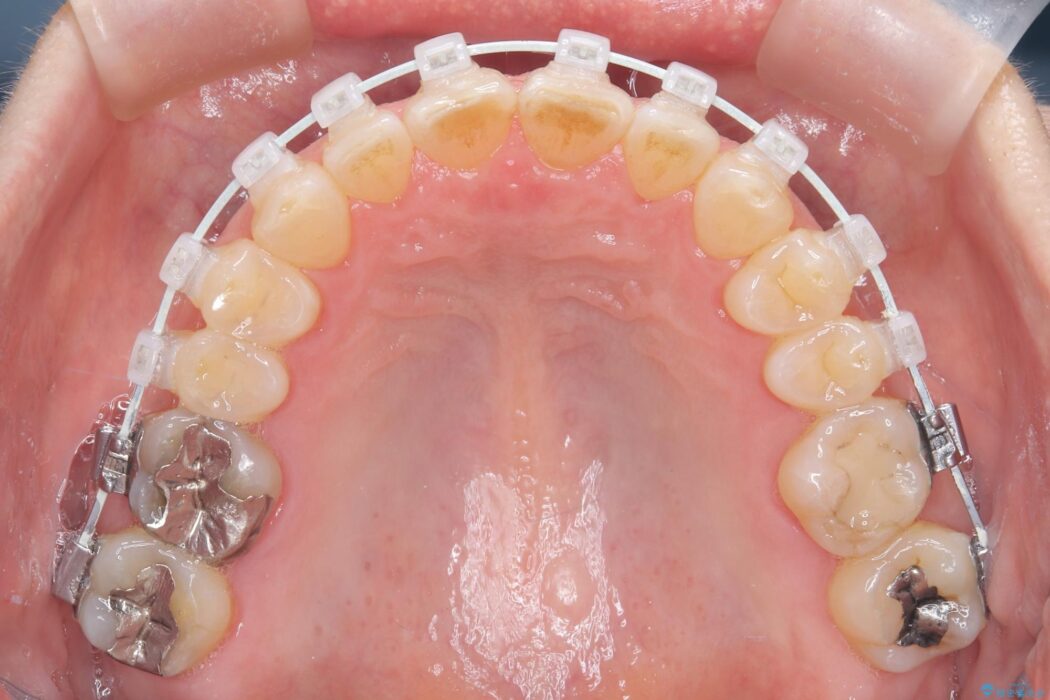

患者様のご希望と状態に合わせ、目立ちにくい審美ワイヤーにて治療を行うこととしました。

スペース確保は、奥歯を少し後ろへ動かす遠心移動と、歯の側面をわずかに削るIPRを併用し、約1年間での治療完了を目指しました。

今回の矯正治療では、歯の色に近い目立たない審美ブラケットとワイヤーを使用しました。

ワイヤー矯正ならではの確実な歯のコントロールにより、当初の計画通り約1年という短い期間で、前歯のガタつきが解消。見た目が美しく整っただけでなく、清掃しやすい機能的な歯並びを獲得していただけました。